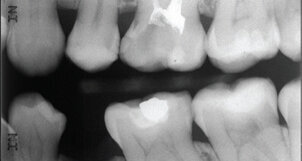

Το πρόγραμμα διάρκειας 90 λεπτών, που συστάθηκε από τη F.Clarke και τους καθηγητές Scully, Saman Warnakulasuriya είναι διαδραστικό με βίντεο και παρουσιάσεις και στοχεύει να αποτελέσει μία ευρεία πηγή γνώσης για τη νόσο για κάθε οδοντίατρο. Το πρόγραμμα χωρίζεται σε 4 θεματολογίες: Τα γεγονότα, Η ομαδική προσέγγιση, Η διαδικασία εξέτασης και η Μελέτη Περιπτώσεων. Υπάρχουν τμήματα επικοινωνιακών τεχνικών-όπου συζητάται η πρόληψη του καρκίνου με ασθενείς, ενημερωτικά βίντεο για πραγματοποίηση μίας ενδοστοματικής εξέτασης, κλινικές εικόνες και πληροφορίες για τα σημεία που μπορεί να υποδεικνύουν την ύπαρξη καρκίνου και παρουσιάσεις για την ανάπτυξη της νόσου.